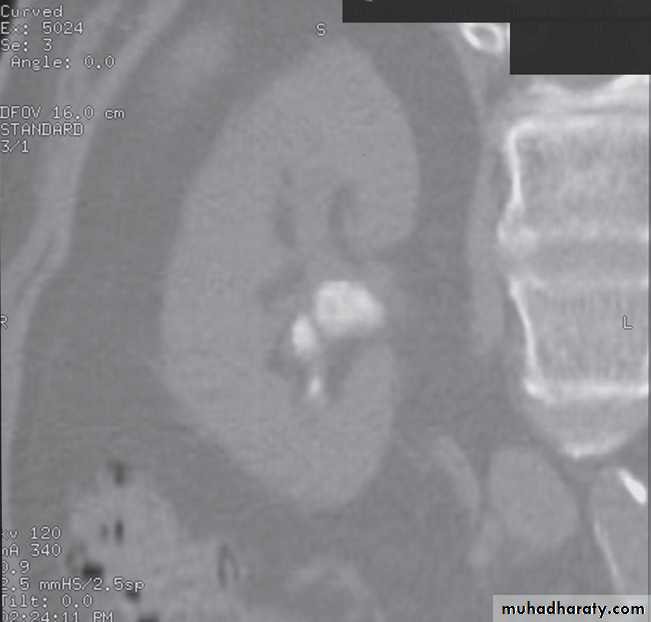

Computed tomography without intravenous contrast medium is exquisitely sensitive for the detection of calculi.

It is used in place of IVU for the detection and precise anatomical localization of stones prior to treatment in most centres

Computed tomography is now widely used to evaluate urinary tract obstruction .In acute obstruction, non-contrast enhanced CT sensitively demonstrates calculi and the unopacified, dilated collecting system can frequently be traced down to the point of obstruction .

At CT their fat content allows a confident diagnosis (Fig. 8.32b, c).